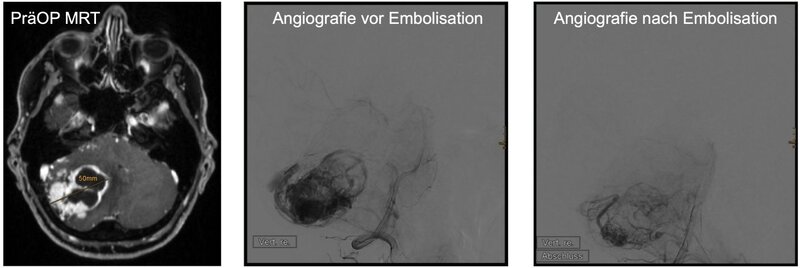

Präoperative Embolisation: Die soliden Tumoranteile der Hämangioblastome sind stark vaskularisiert. Bei größeren soliden Tumoranteilen (ab 2,5 cm Durchmesser) kann vor der operativen Entfernung eine Embolisation des Tumors sinnvoll sein. Hierbei stellen die Kollegen der Neuroradiologie zunächst im Rahmen einer Angiografie die Tumor-assoziierten Blutgefäße dar und können diese dann mit speziellen Materialien präzise verschließen (embolisieren).